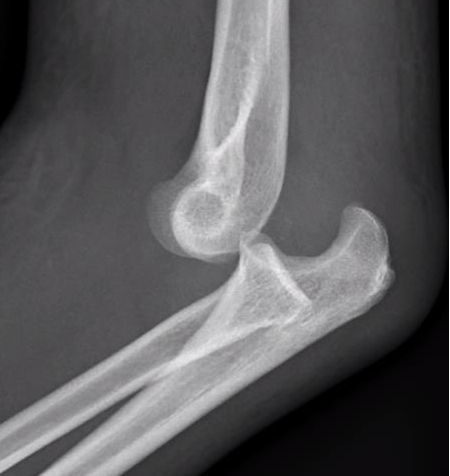

Perched elbow dislocation / subluxation

| Tear LCL | Tearing of anterior capsule |

Posterolateral rotatory subluxation / instability

Incomplete posterolateral dislocation Coranoid perches on trochlea |